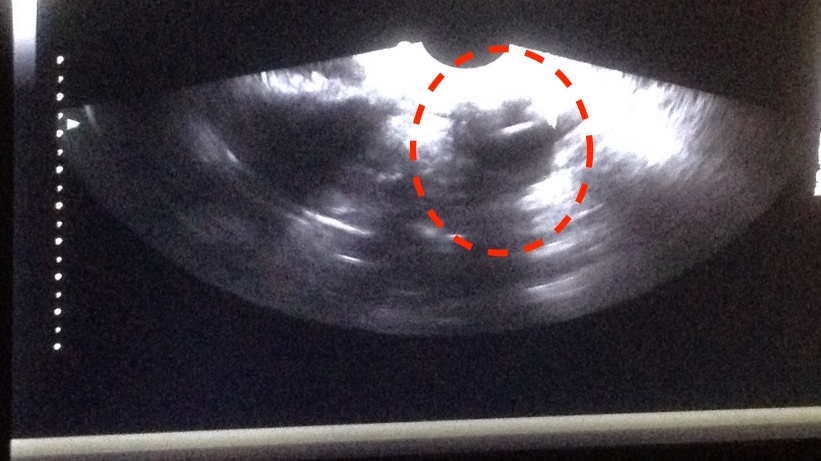

The doctor pointed out that there was a nice big follicle there. Apparently I should have went to school for this because I was having a hard time telling what anything was!

Because of my difficulties seeing what in the world he was talking about, I had him show me on the screen. He had some cursors where the red circle is in the above picture. Woohoo – follicles! Eye on the prize! I got dressed and we were on our way to checkout.